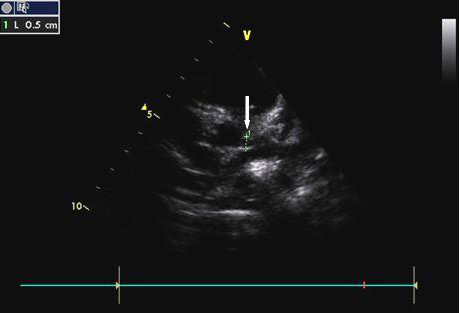

الموجات فوق الصوتية ثنائية الأبعاد هي التقنية المفضلة سوآءا للتشخيص او للمراقبة، بسبب طبيعتها غير الغازية ، وحساسيتها العالية (100٪) وخصوصيتها (96٪) للكشف عن تمدد الأوعية الدموية على مستوى جذوع الشريان التاجي القريبة.

في حالة عدم وجود مضاعفات، يجب إجراء تخطيط صدى القلب عند التشخيص، ثم بعد ذلك بأسبوعين، وأخيرًا بعد ستة إلى ثمانية أسابيع من بداية المرض. ومن جهة اخرى، هناك حاجة إلى المزيد من الاختبارات المتكررة لمتابعة الحالات عالية الخطورة.